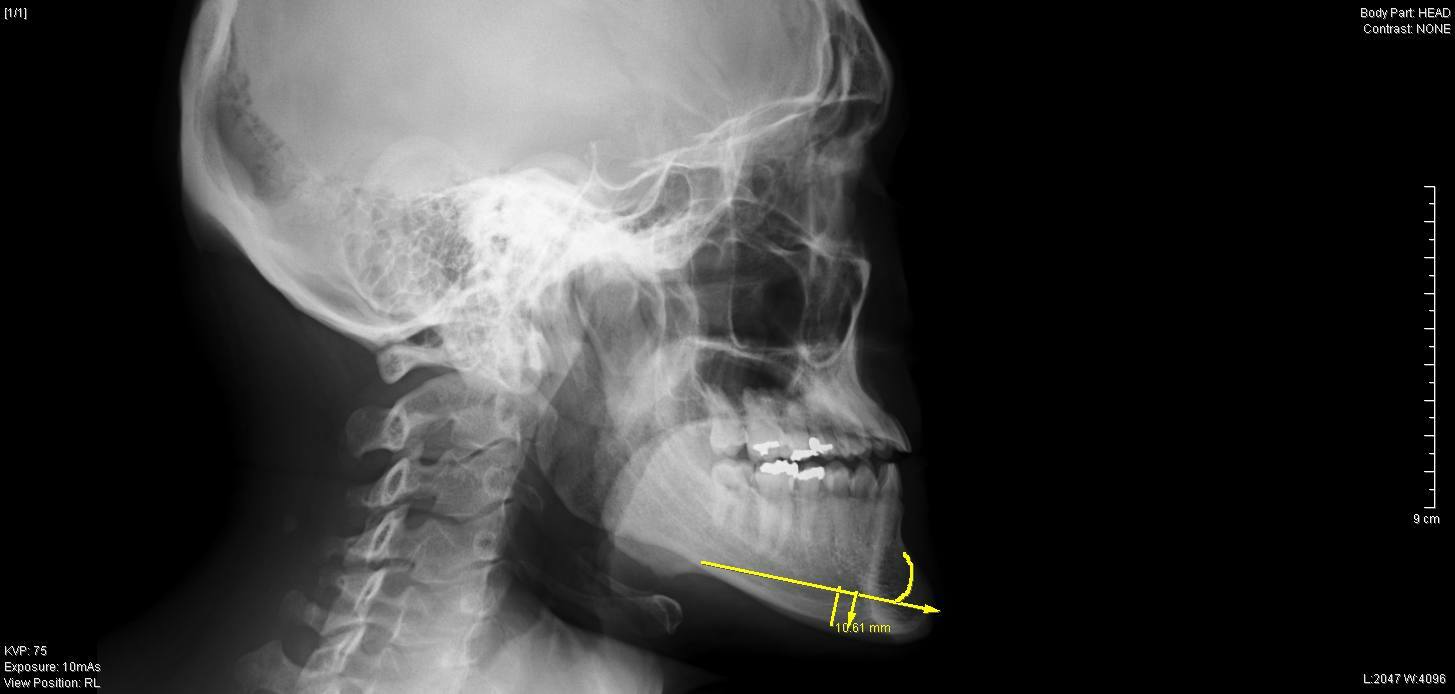

【骨切り手術前 右横】

レントゲンでは、上下方向の切除幅は約1cm、

それに加えEラインを考慮して、

右側 最大 10mm

左側 最大 9mm

先端部 7mm